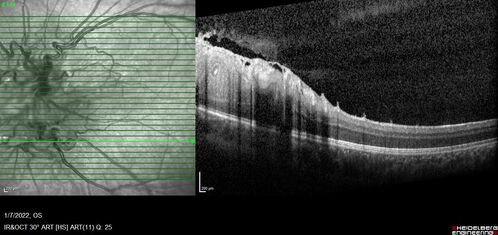

Combined hamartoma of the retina and retinal pigment epithelium

8 year old boy failed vision screening at school. VA 20/20 OD, 20/40 OS

Combined hamartoma of the retina and the retinal pigment epithelium